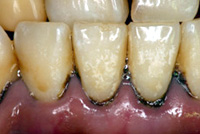

歯と歯ぐきの間の汚れを除去できません |

歯と歯ぐきの間の汚れを除去し、清潔な状態にできます |

歯石除去前 |

歯石除去後 |

歯と歯ぐきの間の汚れを除去できません

歯と歯ぐきの間の汚れを除去し、清潔な状態にできます

歯石除去前

歯石除去後